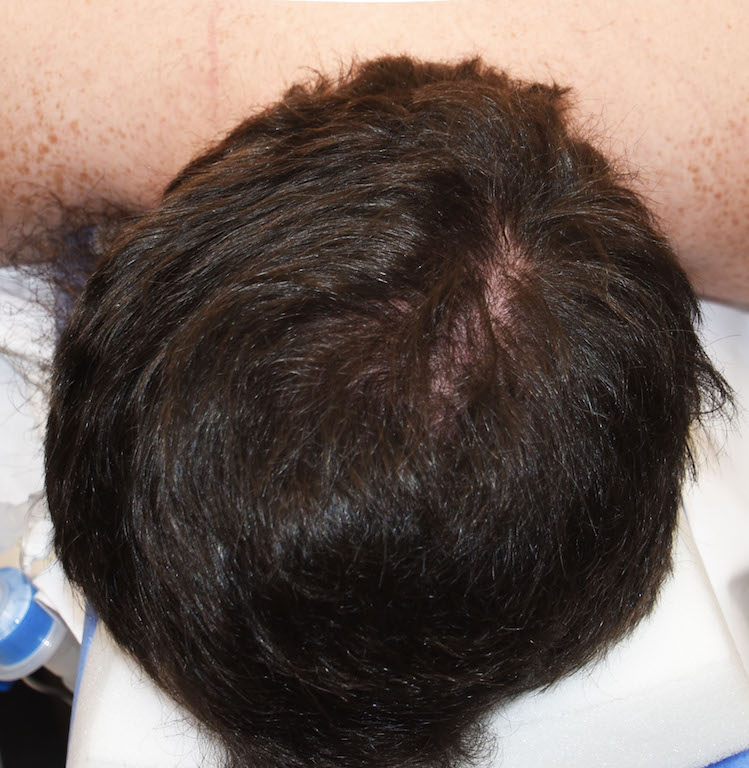

Desire for reduction of sagittal crest that became apparent over the with thinning of the hair.

Mid-sagittal crest skull prominence reduced through a limited scalp incision using high speed burring and large toothed rasps.

Desire for reduction of sagittal crest that became apparent over the with thinning of the hair.

Mid-sagittal crest skull prominence reduced through a limited scalp incision using high speed burring and large toothed rasps.